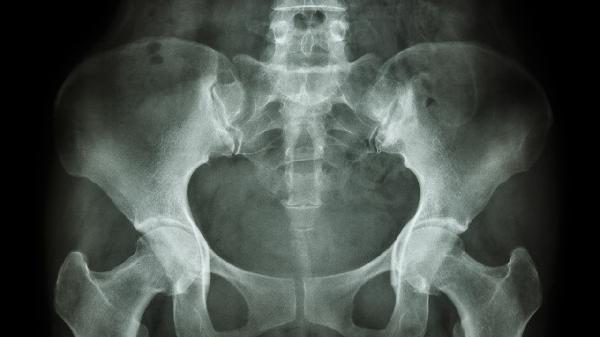

出现耻骨疼痛时应记录疼痛特点和伴随症状,避免自行服用止痛药掩盖病情。建议穿着宽松衣物减少局部压迫,坐卧时使用软垫缓冲。饮食上注意补充蛋白质和钙质,可适当食用牛奶、鱼类、豆制品等。若疼痛持续加重或出现发热、排尿异常等症状,需及时就医进行骨盆超声、X光或MRI检查明确病因。产后女性可进行专业的骨盆康复训练帮助恢复。